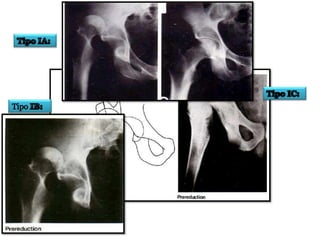

CLASIFICACION DE

THOMPSON Y EPSTEIN

• Tipo I: Luxación posterior pura o con minima fractura

de la ceja acetabular.

• Tipo II: Luxación posterior con una fractura mayor d la

ceja acetabular posterior.

• Tipo III: Luxación posterior y fractura conminución de

la ceja acetabular con o sin fragmento mayor.

• Tipo IV: Luxación posterior con fractura del piso

acetabular.

• Tipo V: Luxación posterior con fractura de la cabeza

femoral.